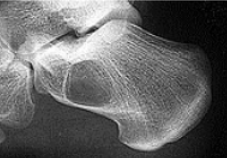

What disease is this? What does the arrow indicate? | Rheumatoid arthritis. Arrow = Bone erosion secondary to inflammation of retrocalcaneal bursa. |